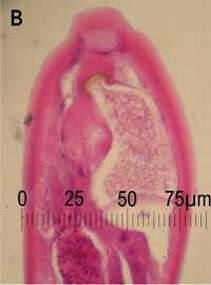

The patient revealed that 4 weeks before symptom onset, he had taken care of a pet goat at his house, and had used fresh goat manure as fertiliser for his lettuce and other vegetable seedlings. He ate the garden produce raw and unwashed. A sample of the goat faeces was obtained from the garden for examination (fresh samples were unavailable). Baerman isolation and iodine fixation of the goat stool showed larvae of various stages, including rhabditiform larvae (probably from soil contamination) and ensheathed larvae (presumed to have hatched from eggs which would have been present in a fresh specimen). A Trichostrongylus colubriformis larva is shown in Box 3.

Trichostrongylus species are zoonotic nematode parasites, ubiquitous among herbivorous mammals worldwide. Human infection is most common in herders of sheep and goats, but may potentially be acquired from contact with faeces of other infected host animals such as cattle, camels and donkeys.2 Isolated cases or small series in humans have long been recognised in Australia: 60 cases were reported from Queensland by the Hookworm Campaign between 1923 and 1928, and more recently, five cases were detected out of 46 000 stool examinations at a Queensland laboratory between 1992 and 1995.3-7 Human prevalence data are difficult to acquire because misclassification is common, and symptoms may be mild or non-existent. Trichostrongylus eggs are most commonly mistaken for hookworm eggs, which have a similar shape, although the former are larger (73–94 × 40–53 μm), and slightly pointed at one or both ends (Box 3).2 Misidentification occurred twice in Patient 1; eggs were initially identified as those of hookworm, and adult worms seen on endoscopic biopsy as Enterobius vermicularis. Diagnostic difficulties also arise because of the long prepatent period. Even after the period of maturation from larval stage to egg-laying adults, passage of eggs may still be scanty or undetectable for some time (with reported delays of 4 months to 2 years between symptom onset and detection of eggs2,5). This probably explains the absence of detectable eggs in the stool specimens of Patient 2.

Adult Trichostrongylus parasites residing in the gut of an infected host produce eggs which hatch in faeces to produce larvae. Such larvae (Box 3) are difficult to distinguish from those of another parasitic genus infecting goats, Ostertagia (an organism which is non-pathogenic to humans), and may be difficult for anyone other than a trained parasitologist to distinguish from larval forms of hookworm or Strongyloides. Identification of these parasite species is usually based on features of the adult worm. The larvae pass through two free-living stages to become infective third-stage larvae. These larvae are motile and migrate to vegetation and are ingested when the vegetation is eaten. The third-stage larvae then exsheath and move to the duodenal mucosa, mature into adult worms over about 25 days, and live among the intestinal villi and mucus. Patients may be asymptomatic, with eosinophilia only noted incidentally. When symptoms are present, they are confined to the gastrointestinal tract, as there is no migratory phase. A high worm burden can lead to marked eosinophilia, desquamation of gut mucosa, and severe symptoms including epigastric pain and diarrhoea.2 The per rectum bleeding noted in Patient 1 is likely to have been a direct result of mucosal inflammation and trauma caused by adult worms attaching to intestinal epithelium.

3 Trichostrongylus colubriformis larva

Trichostrongylus colubriformis third-stage larva obtained after culture of faeces from an artificially infected sheep.